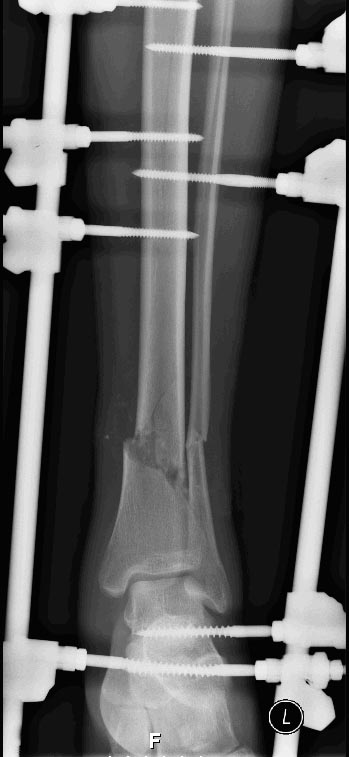

Открытый перелом обеих костей н/3 левой голени, типа Gustillo 2a, повреждение сухожилий разгибателей пальцев стопы.Обстоятельства ранения - диск пилы по дереву. Пациент 22 года.

Послеоперационная рана зажила первичным натяжением, операция сделана 01.01.2013. Наложен АНФ.